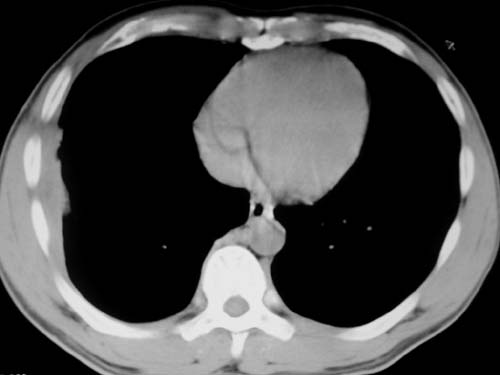

标题: CT19540: 31岁。自述结核性胸水治疗两个月后,在外院拍x线发 [打印本页]

标题: CT19540: 31岁。自述结核性胸水治疗两个月后,在外院拍x线发

右侧胸壁结节状软组织影伴相应肺叶内受侵,伴右侧胸腔积液。考虑:结核性可能大。

1、炎性包块;2、右侧少量胸膜积液。

1、炎性病变,结核可能;2、右侧少量胸膜积液。

右侧胸壁结节状软组织影伴相应肺叶内受侵,伴右侧胸腔积液,结合临床,首先考虑结核。

考虑结核性胸膜炎,胸膜肥厚,不除外胸膜间皮瘤可能,建议复查。

1)考虑右侧结核性胸膜结节。2)右侧胸膜增厚+包裹性胸腔积液。

结核性脓胸、肺内结核?